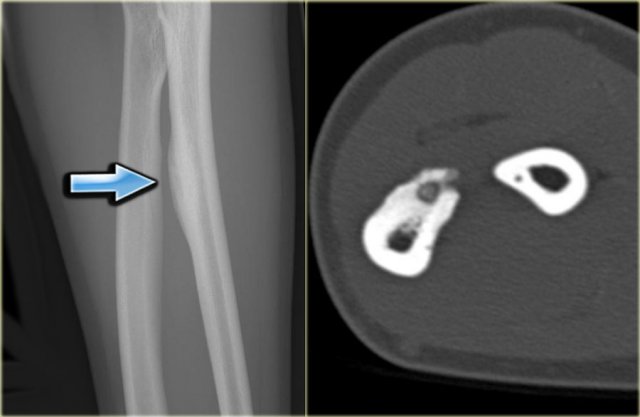

Study the image and then continue reading.

The findings are:

• A well-defined and homogeneous sclerotic mass with a broad base to the underlying diaphysis of the fibula.

A juxtacortical or parosteal osteosarcoma should be considered, particularly when a history of trauma is lacking.

Final diagnosis: parosteal osteosarcoma